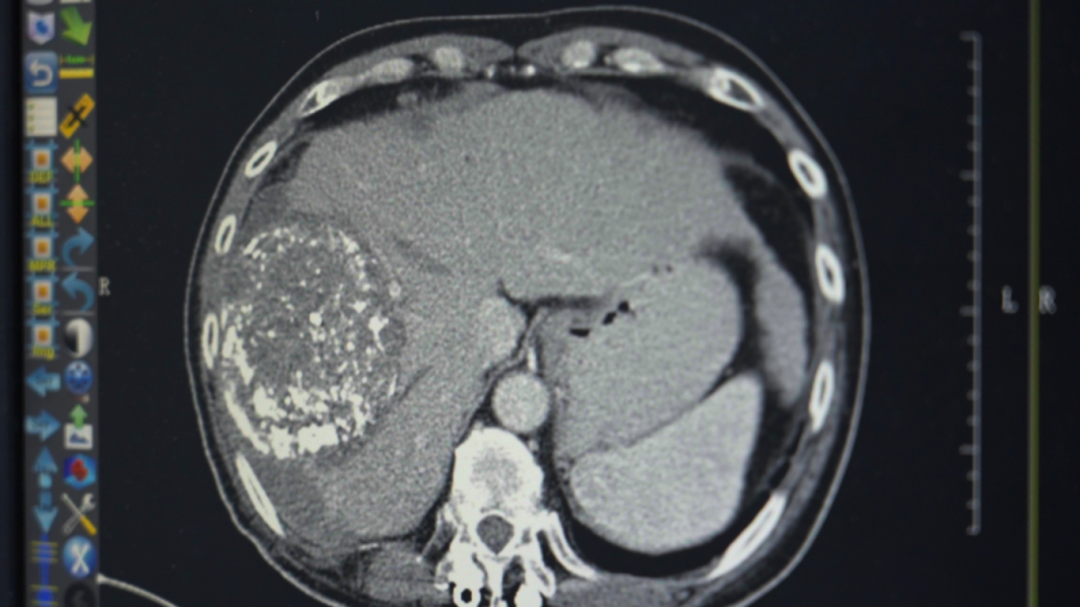

在当地医院,勇哥接受了一次介入灌注化疗栓塞术,但反应剧烈,“反复发烧,烧了足足半个月”。好不容易烧退了,复查结果却更令人绝望:肝脏病灶扩大到13.2厘米,肺转移瘤增多,肝门区、腹腔淋巴结密密麻麻。医生跟他说肿瘤扩散太广,无法手术,最多只剩“两个月时间”。

第三次回院复查时,勇哥的甲胎蛋白已降至800多,CT显示肝癌及肝内多发转移瘤、双肺转移瘤及大网膜转移瘤都较前缩小,无新发病灶,病情评价为稳定(SD)。“这次做介入治疗时,医生告诉我肝上肿瘤基本没有活性了。”勇哥的声音中带着久违的轻松。